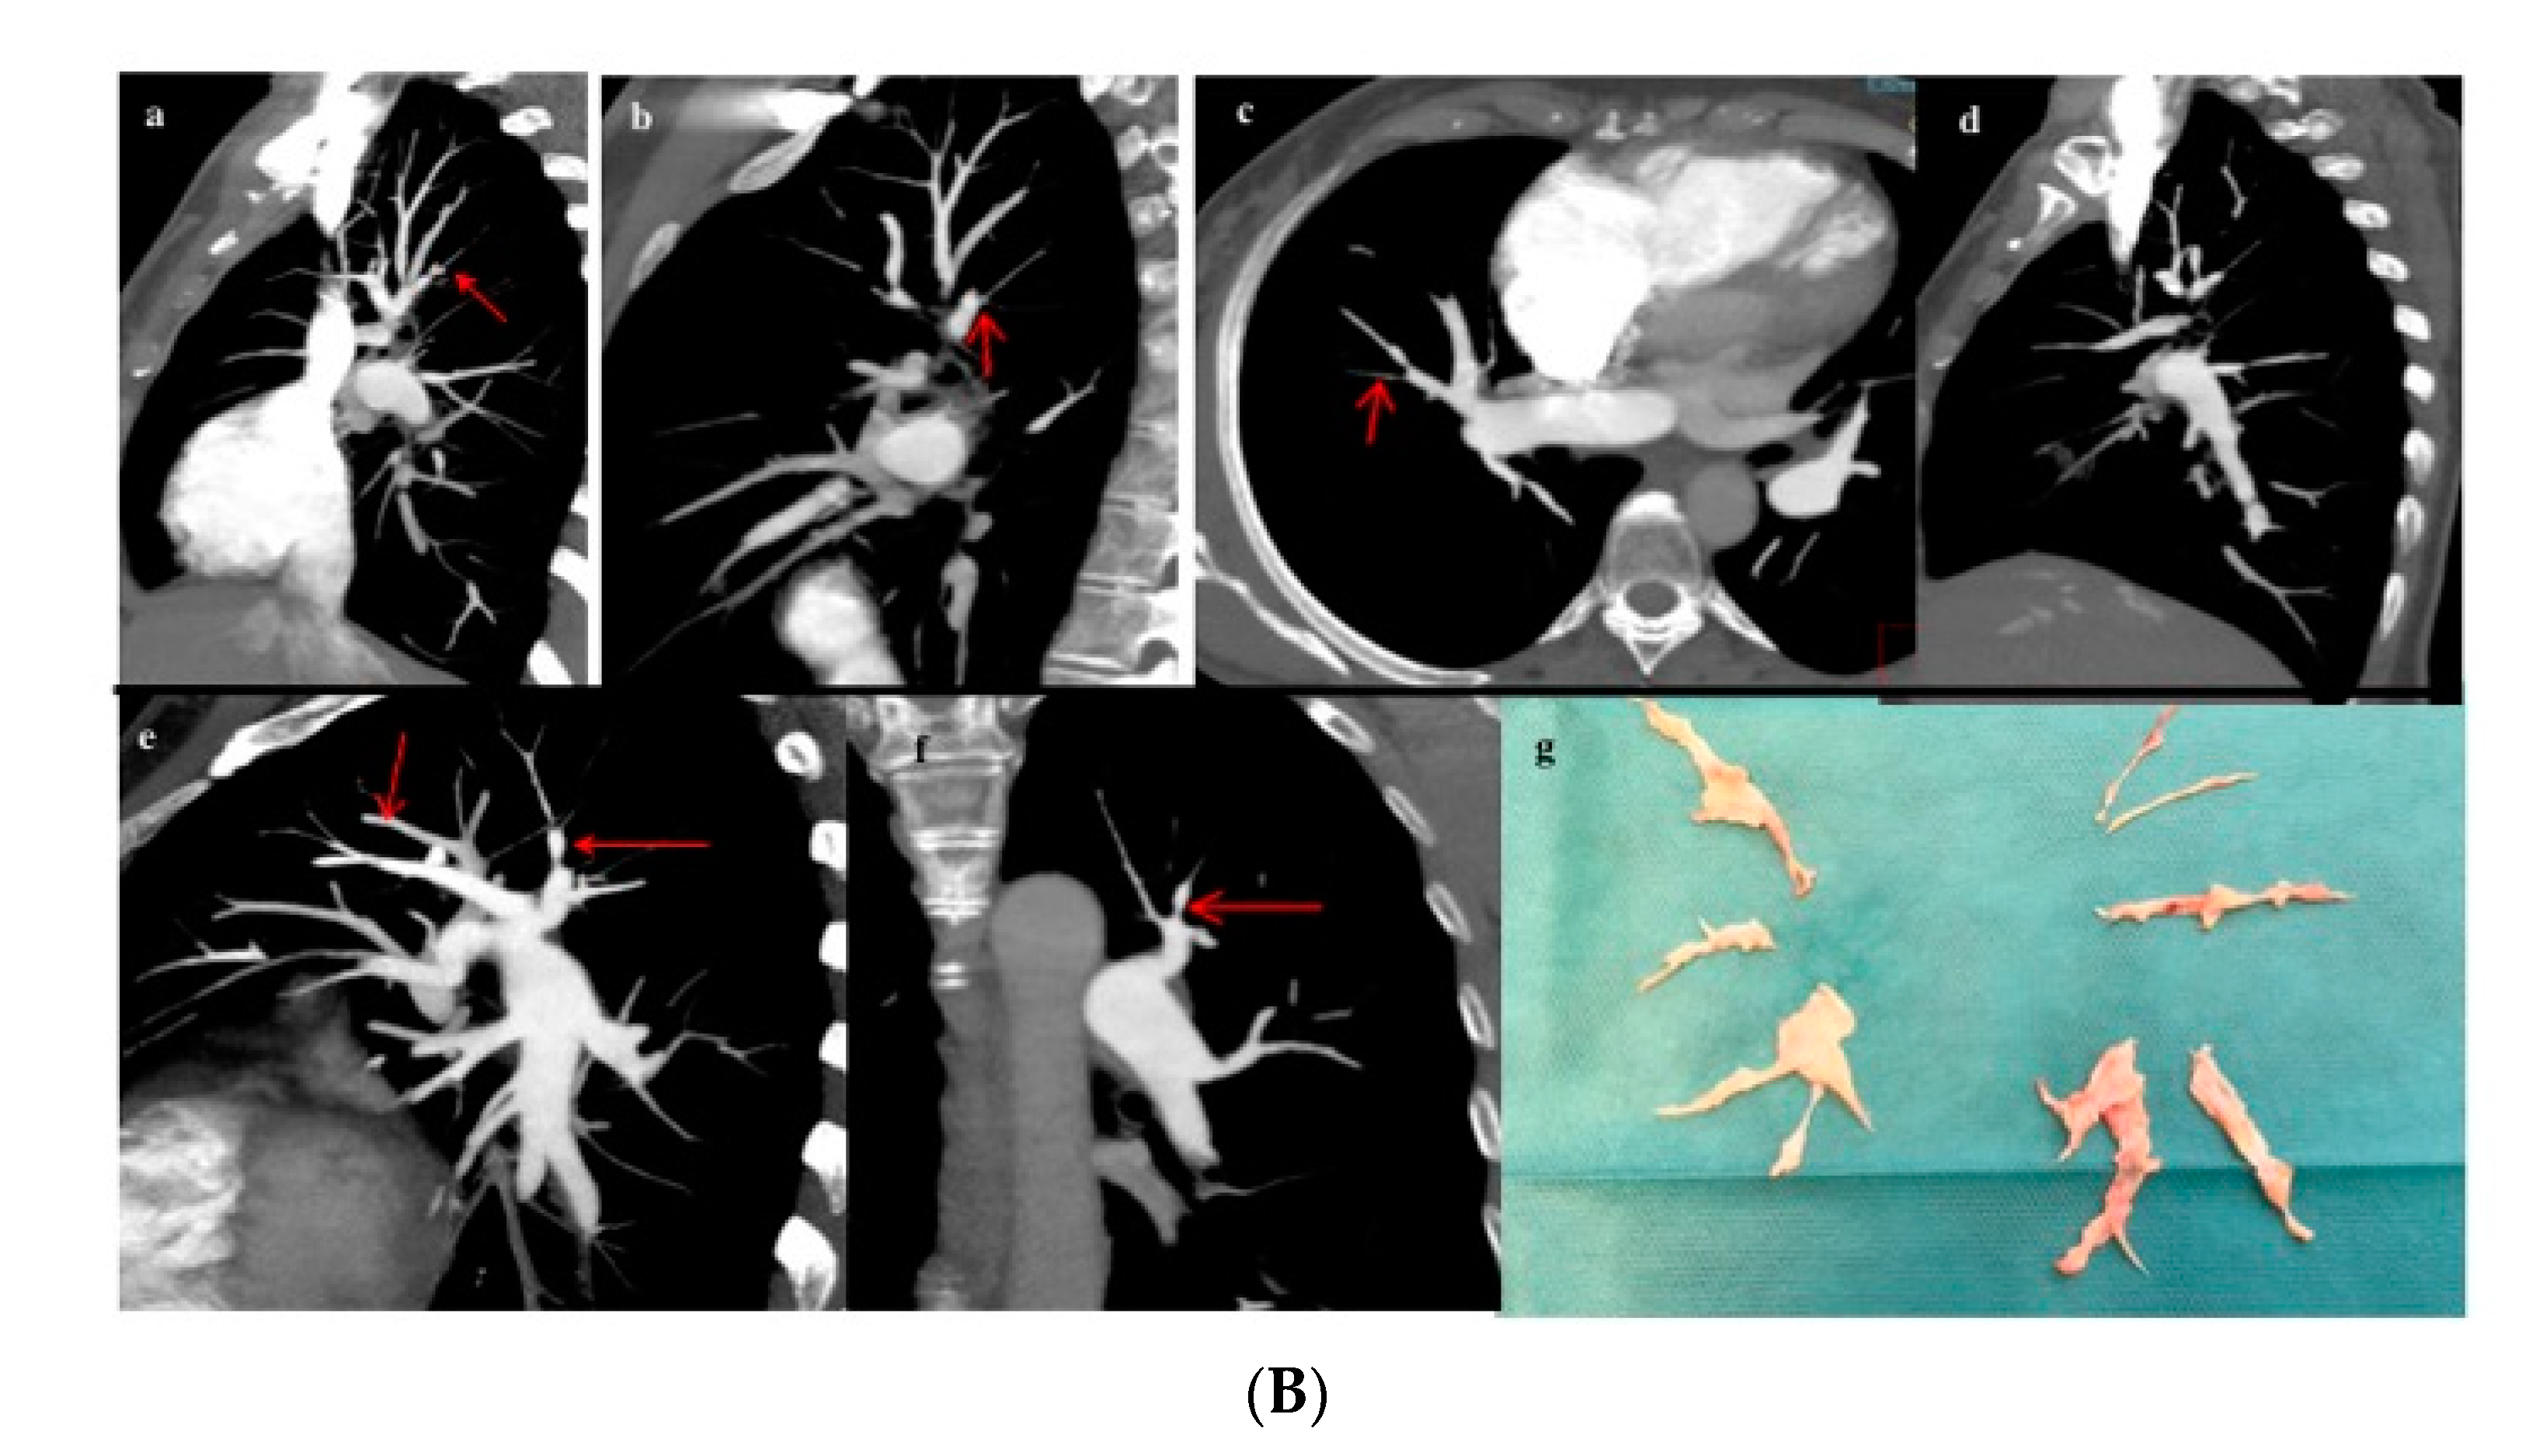

Figure 5.

Patient with proximal CTEPH (A). (a,b) Rectified interventricular septum (red thin arrow) and reduction of venous return (*). (c–e) Thromboembolic disease affecting the main pulmonary artery (red thick arrow) with extension to the right upper lobar artery (arrowhead). (f) Surgical specimen showing level I disease. Patient with distal CTEPH (B). (a–f) Organized intravascular material (thin red arrows) is identified at distal-segmental/subsegmental levels in all the pulmonary lobes. (g) Surgical specimen showing level III disease.

Amidst those patients who underwent PEA (n = 91), 18.7% had level I disease (Figure 5A), 45.1% level II disease, and 36.3% level III disease (Figure 5B). Table 1 summarizes the proportion of intervened patients for whom the surgical decision was based on MCTA compared with those who needed a complementary PA regarding intraoperative CTEPH classification. In up to 54% of intervened patients with level III disease, a decision on operability had been made exclusively on MCTA.